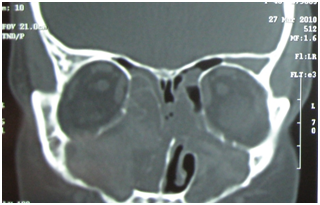

Plain X-rays of the paranasal sinuses are almost obsolete now. CT scan of nose and paranasal sinuses will show the extent of nasal polyp, changes in the sinuses and anatomical variations, which are important considerations if surgical treatment is planned. Coronal CT is the standard view, which provides the required information in most of the cases. Axial view may be required in some cases, especially those with complications. The most important advantage of CT scanning is the precise view of the sinuses and ostiomeatal complex.2 Nasal polyposis will be seen as homogenous soft tissue opacity in the nasal cavity and involved paranasal sinuses (Figure 2). In case of allergic fungal sinusitis, there will be heterogenous soft tissue opacity within the sinuses (Figure 3). Several staging methods have been described for assessment of the degree of inflammatory changes in paranasal sinuses on CT scan, the most commonly used is the Lund-Mackay system. 6

Figure 2 CT scan Nose and Paranasal sinus, showing an Antrochoanal polyp in right nasal cavity.